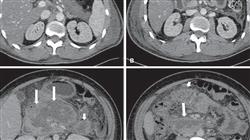

الأمراض الكبدية والبنكرياسية تظهر سريريًا بطرق متنوعة، مع ظهور الأعراض والعلامات المحلية بشكل لافت للنظر وهناك مظاهر بعيدة أو جهازية مرتبطة بتدهور وظائف العضو. غالبًا ما تتميز المظاهر السريرية لأمراض هذه الأعضاء بالعامل المسبب، والذي غالبًا ما يكون معديًا أو سامًا، أو أحيانًا حتى من خلال تكوينها المرضي.